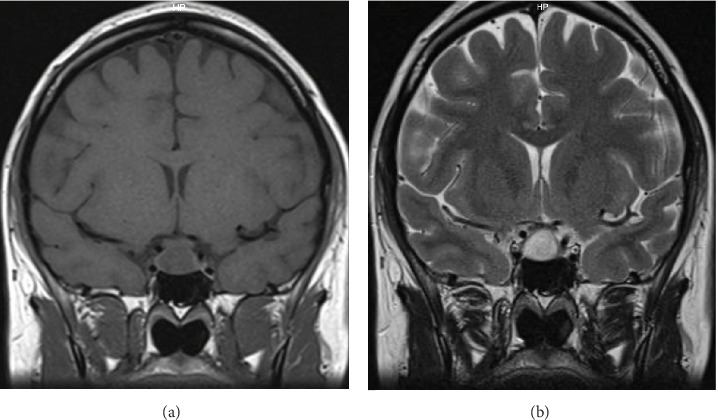

催乳素瘤是垂体腺瘤中最常见的亚型,是导致女性闭经和不孕的主要病因之一。主要的治疗方法需要使用多巴胺激动剂,有效地恢复生育能力。在微泌乳素瘤的病例中,在怀孕期间出现症状性肿瘤扩大的可能性非常低,估计只有2.4%。因此,一旦成功怀孕,停用多巴胺激动剂,并对患者的病情进行持续的临床监测。妊娠期脑垂体中风的发生率极为罕见。我们提出一个病例29岁的患者与微泌乳素瘤,治疗卡麦角林,这是停止在实现怀孕。然而,在妊娠第16周,她出现了持续的头痛和视力下降,表现为左颞偏视。非对比磁共振成像(MRI)显示腺瘤增大,并伴有出血的迹象。她在怀孕26周时被转介到我们医院。卡麦角林治疗恢复,患者耐受良好。剂量增加到每周2毫克,因为双颞偏视没有改善。妊娠35周进行的非对比MRI扫描显示腺瘤尺寸进一步增大,尺寸为17 × 21 × 13 mm,并有瘤内出血的迹象。在妊娠39周进行了有计划的剖宫产手术,没有遇到母胎并发症。由于腺瘤压迫交叉,没有开始母乳喂养。因此,继续使用多巴胺激动剂治疗。在产后随访期间,患者经历了月经周期恢复,催乳素水平正常化,肿瘤大小缩小。最终,诊断确定为微泌乳素瘤,在怀孕期间由于垂体瘤中风而扩大。虽然微泌乳素瘤在妊娠期间通常具有较低的症状性肿瘤生长风险,但本病例强调了警惕的临床监测对迅速发现和处理这种罕见并发症的重要性。这个例子作为一个不常见事件的教育例子-微泌乳素瘤在怀孕期间经历中风。

Prolactinomas are the most prevalent subtype of pituitary adenomas and represent one of the leading etiological factors responsible for amenorrhea and infertility in women. The primary therapeutic approach entails the use of dopamine agonists, which effectively restore fertility. In cases of microprolactinomas, the likelihood of experiencing a symptomatic enlargement of the tumor during pregnancy is exceptionally low, estimated at a mere 2.4%. Consequently, once pregnancy is successfully achieved, the administration of dopamine agonists is discontinued, with ongoing clinical monitoring of the patient's condition. The incidence of pituitary apoplexy during pregnancy is exceedingly rare. We present a case of a 29-year-old patient with microprolactinoma, treated with cabergoline, which was discontinued upon achieving pregnancy. However, at the 16th week of gestation, she presented with persistent headaches and compromised visual acuity, manifesting as left temporal hemianopia. A noncontrast magnetic resonance imaging (MRI) revealed an enlargement of the adenoma, accompanied by evidence of hemorrhage. She was referred to our hospital at 26 weeks of gestation. Cabergoline treatment was reinstated and well tolerated by the patient. Doses were increased to 2 mg per week because bitemporal hemianopia was not improving. A subsequent noncontrast MRI scan performed at 35 weeks of gestation demonstrated a further increase in adenoma size, measuring 17 × 21 × 13 mm, with signs of intratumoral bleeding. A planned cesarean section was performed at 39 weeks of gestation, without encountering maternal-fetal complications. Breastfeeding was not initiated due to the adenoma's compression of the chiasm. Accordingly, dopamine agonist therapy was continued. During the postpartum follow-up, the patient experienced a resumption of menstrual cycles, normalization of prolactin levels, and a reduction in tumor size. Ultimately, the diagnosis was established as a microprolactinoma, which had enlarged during pregnancy due to a pituitary tumor apoplexy. Although microprolactinomas typically carry a low risk of symptomatic tumor growth during pregnancy, this case emphasizes the critical importance of vigilant clinical monitoring to swiftly detect and manage this rare complication. This instance serves as an educational example of an uncommon event-a microprolactinoma experiencing apoplexy during pregnancy.